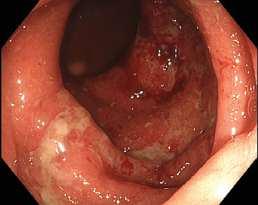

Obr. . Nález v rektu – erytém, kyprá sliznice.

Fig. . Findings in the rectum – erythema, loose mucosa.